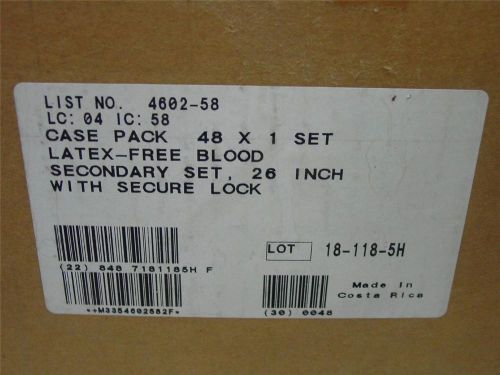

1 case qty 48 I.V. Set 4602-58 abbott Plum omni-flow pumps